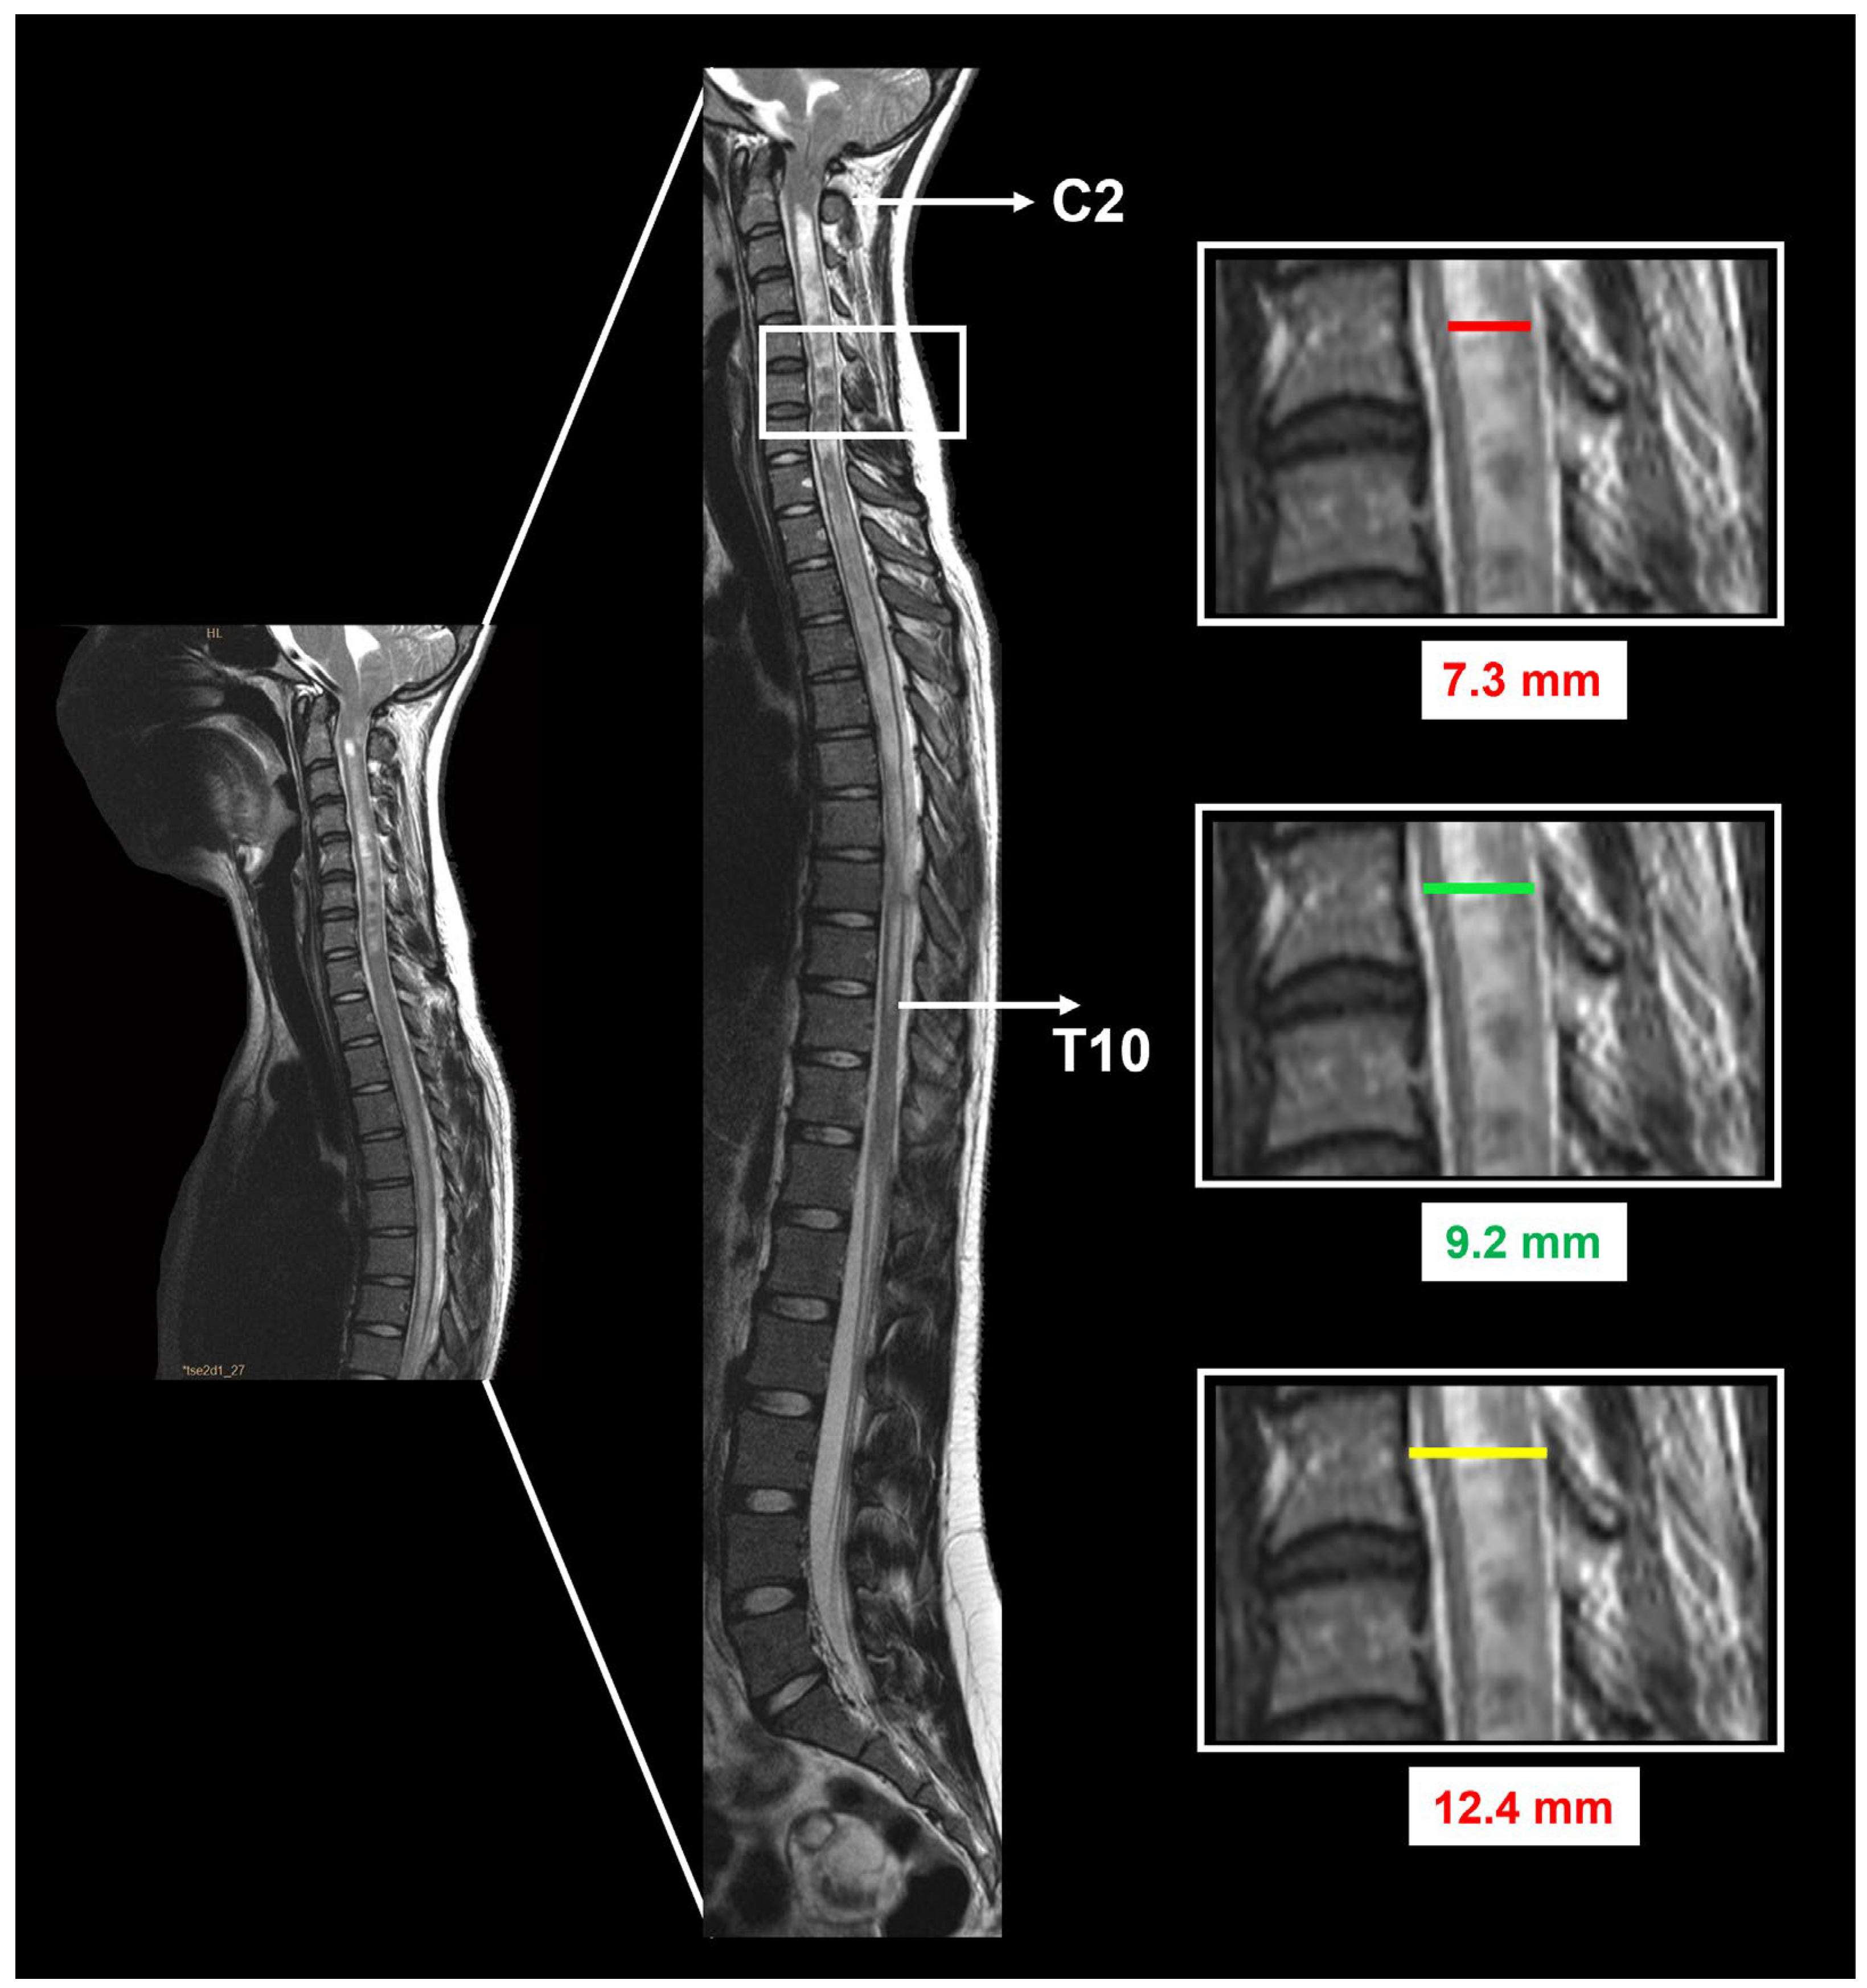

3.5. Neuroimaging Findings before and after Surgery